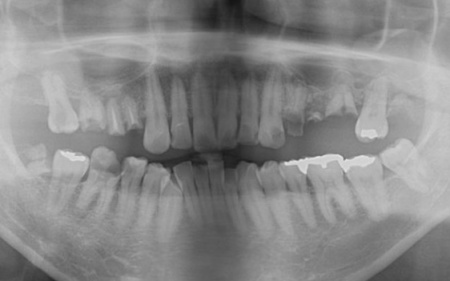

40代男性 温存が難しい複数の歯を抜いてインプラントブリッジで修復した症例

「ブリッジが外れたまま放置していた。また、前歯が欠けているのが気になる」とご相談いただきました。

拝見したところ、上左右の奥歯には、歯が失われていたり欠けたりしている部位が複数確認されました。

患者様によると、以前上顎にはブリッジ(両隣の歯を支えとして欠損部を補う装置)が装着されていましたが、10年前に外れたきりそのままの状態で過ごしていたとのことでした。

痛みがなかったため、とくに治療は受けていなかったようですが、以前から前歯の一部が欠けていることが気になっており、見た目や将来のお口の健康に不安を感じていたそうです。

そこで、詳しく検査を行った結果、欠けたり傷んだりしている歯が複数見つかり、さらに歯茎や歯を支える骨にも問題が生じていました。

とくに、右上奥歯は前から4番目と6番目の歯、左上奥歯は前から4番目・5番目・6番目・8番目の歯が著しく傷んでおり、温存が難しいと考えられます。

また、右下の一番奥の歯(親知らず)は歯の根だけが残り、細菌感染が広がるリスクが高い状態です。

その一方で、上前歯や右下奥歯は、適切な処置を行うことで温存できる歯も複数確認できました。

以上のことから、口腔内の状態を改善するためにも必要に応じて抜歯を行い、欠損部位を補う治療が必要だと診断しました。